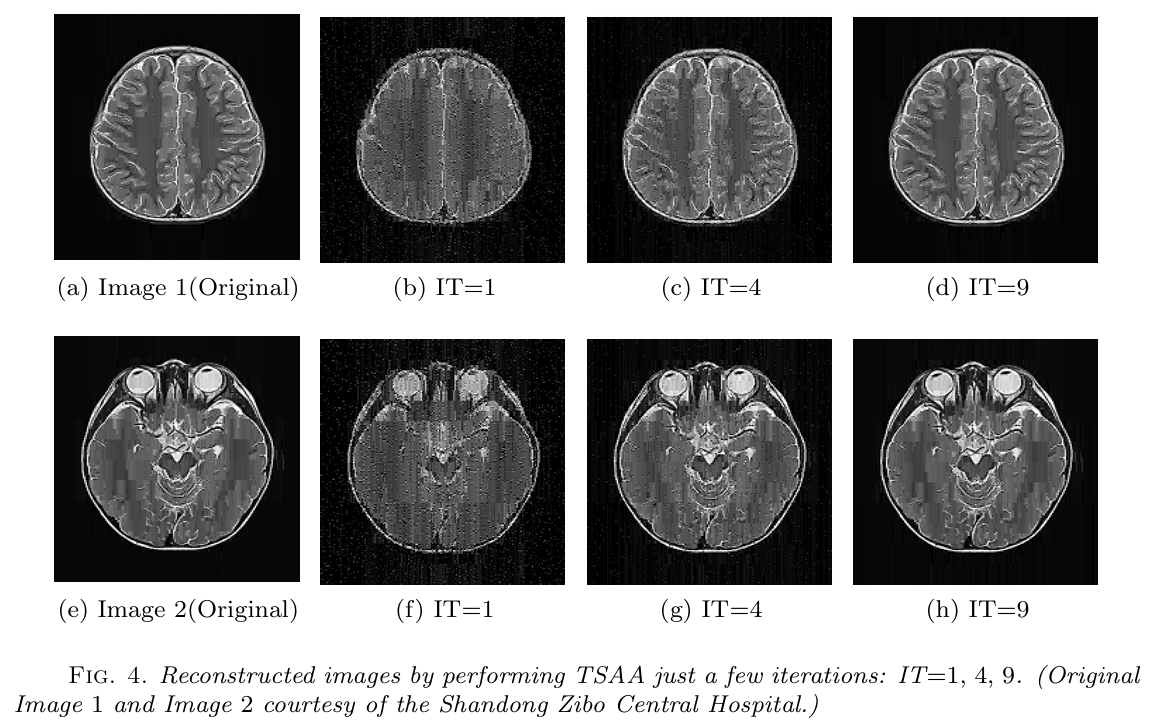

近期,公司运筹学与控制论团队在稀疏线性反问题及其在信号与图像处理的应用方面取得新进展。孙中锋副教授与赵云彬教授(深圳市大数据研究院)、周金川教授、黄正海教授(天津大学)合作的论文“Dynamic thresholding algorithm with memory for linear inverse problems”针对稀疏线性反问题,研发了动态指标选取技术和子问题降维技术,进而提出了记忆动态阈值算法,大幅度降低了最优阈值型算法的计算复杂度,并将其应用于语音信号的重构问题(见图1);赵云彬教授与孙中锋副教授合作的论文“Splitting alternating algorithms for sparse solutions of linear systems with concatenated orthogonal matrices”为解决大规模稀疏线性反问题,基于结构化矩阵提出了分裂算法,将大规模问题分裂成若干小规模子问题进行求解,并将其应用于脑部核磁共振图像(MRI)的重构问题(见图2)。

图2 MRI图像的重构